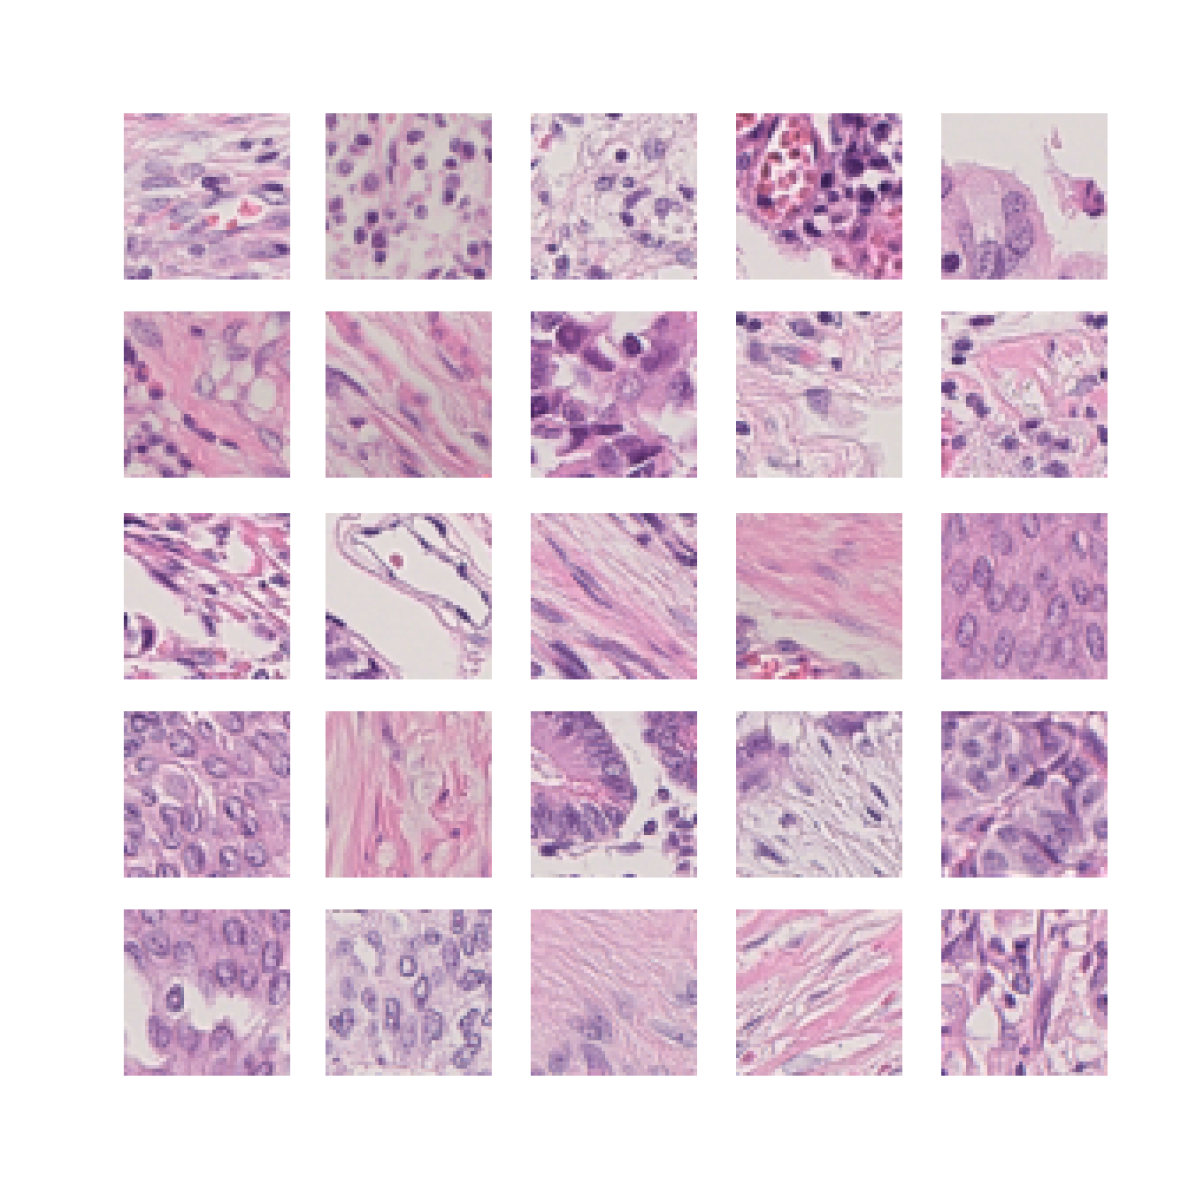

We also analyse the activation maps for each model using GradCAM as described in section S3. This offers more insight into the areas of the image which are contributing most heavily to the models’ representations. In Figure 4(b) we present some representative examples, however, a larger selection which was chosen at random is presented in Figures S10 to S25. The larger selection makes it easier to see the emergent patterns, including that privileged Siamese models tend to mainly identify features which are strongly present in both inputs, while unprivileged Siamese models tend to learn more diffuse features that are not specific to one cell phenotype or image region. TriDeNT ♆ incorporates both sets of features, learning both features specific to the privileged data and more the general features associated with unprivileged Siamese networks.

We can see in Figure 4(b) panel A that for ERG, the privileged Siamese model focuses almost exclusively on any nuclei which could be endothelial cells. As there are very few endothelial cells in the dataset, it could be an effective strategy to identify anything that could potentially be an endothelial cell to minimise the difference between the representations of the H&E model and the IF mask model. In the corresponding unprivileged Siamese image, we see that the model identifies some of these nuclei, albeit less strongly, but also focuses heavily on the other tissue and even the background, while strongly fixating on two spots of debris in the center of the image. This model has less ‘incentive’ to learn the weak features related to endothelial cells as these occur rarely and are not easy to detect, while more generic strong features such as the presence of connective tissue and the prevalence of background are more common and predictable from augmented images. We see that TriDeNT ♆ combines these two feature sets, strongly identifying nuclei while also identifying the connective tissue.

In panel C we see a similar pattern, with the privileged Siamese model fixating solely on the nuclei, while the TriDeNT ♆ model takes a more balanced approach. The unprivileged Siamese model appears to focus on a single cluster of nuclei while neglecting others, and similarly identifies an area of fibroblasts with its distinctive pattern but does not others.

In contrast to panels A and C which represent models with poor privileged Siamese results, panels B and D represent models whose privileged Siamese results were comparable to both TriDeNT ♆ and even the supervised baseline. It is therefore interesting to note that there are far more similarities between the privileged Siamese and TriDeNT ♆ models in both cases. Particularly in panel B, TriDeNT ♆ and the privileged Siamese model return virtually identical heatmaps, with both strongly identifying epithelial nuclei and neglecting the same areas of connective tissue. The unprivileged model in this case appears to focus solely on the centre of the image, giving a significantly different heatmap to the other panels.

Panel D again shows the previous pattern, with the privileged Siamese model identifying the features strongly present in the privileged data – fibroblasts – while neglecting the nuclei present. TriDeNT ♆ also strongly identifies the connective tissue, but, unlike the privileged Siamese model, does not completely neglect the nuclei. The unprivileged Siamese model primarily identifies background, and does not appear to identify the nuclei in this example.